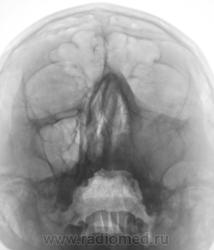

Длительное время лечится по поводу "ринита". Направлен на рентгенографию ППН.

пристеночное затемнение левой верхнечелюпазухи за счет отека и набухания слизистой-катаральный гайморит

Могу предположить гиперплазию слизистой( характерная картинка ( смотрите книги Файзуллина М.Х.) +анамнез (длительное время лечится по поводу "ринита").